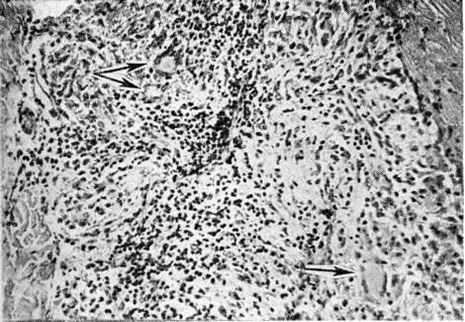

Рис. 3.

Микроскопическая картина кожного инфильтрата при лепроматозном типе лепры: стрелками указаны скопления липидов в цитоплазме лепрозных клеток. Окраска Суданом III; × 500.

Рис. 4.

Микроскопическая картина кожного инфильтрата при лепроматозном типе лепры: стрелками указаны гигантские многоядерные лепрозные клетки. Окраска гематоксилин-эозином; × 640.

Рис. 1—6.

Микроскопические картины поражений при различных формах лепры.